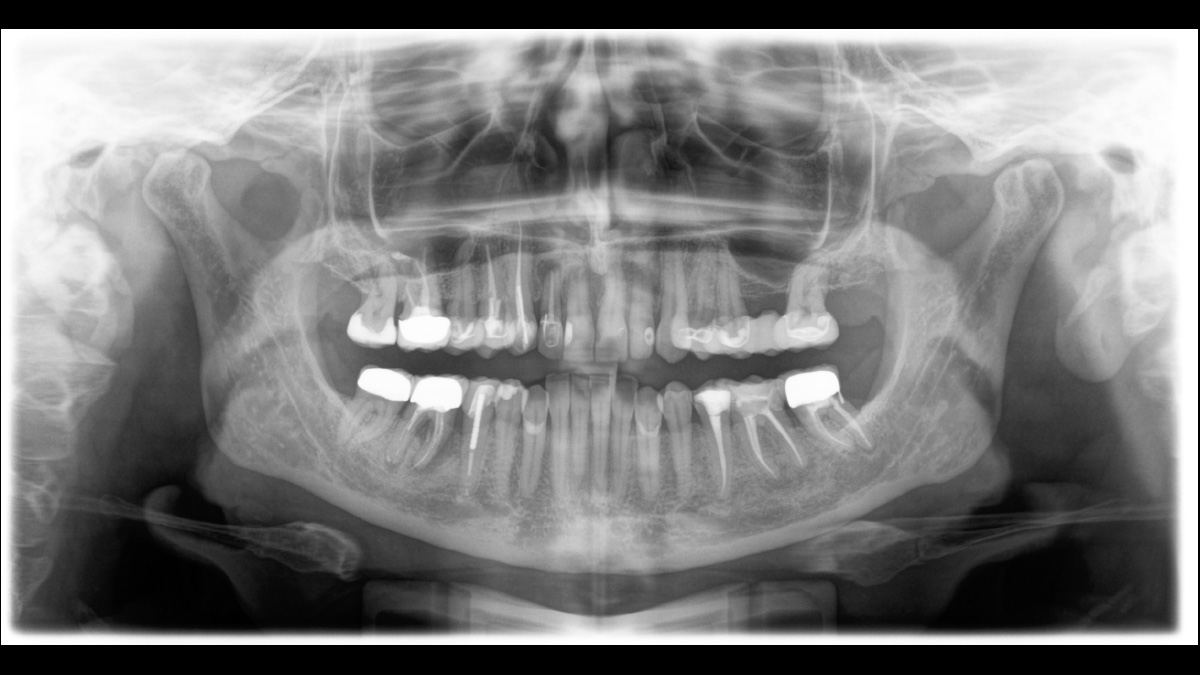

El enfoque correcto es crucial para excelentes radiografías panorámicas. Con la función de autofoco, usted recibirá automáticamente una imagen con la mejor nitidez posible en foco. Los dispositivos de radiología de Dentsply Sirona toman varios miles de imágenes individuales en un ciclo e identifican automáticamente las áreas donde la mandíbula está posicionada de manera óptima. Luego, sin ningún paso manual adicional, estas imágenes se muestran en una nítida imagen final.

Solo algunas partes de la imagen están en foco, mientras que otras áreas están borrosas.

El sistema detecta las áreas relevantes a partir de varios miles de imágenes individuales en un ciclo e identifica automáticamente las áreas donde la mandíbula está posicionada de manera óptima.

Imágenes nítidas.